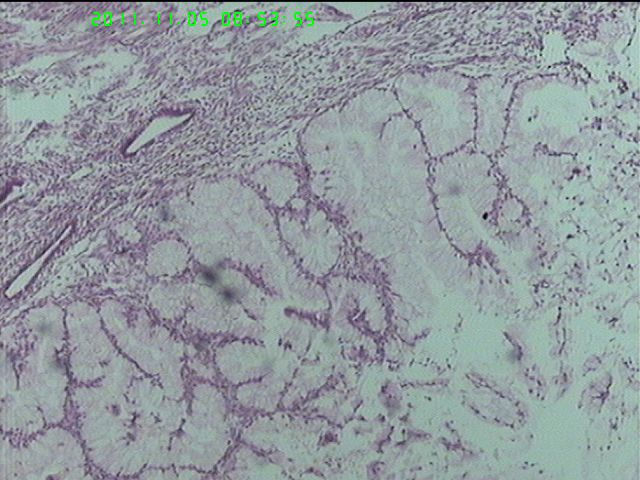

37岁女性患者,左卵巢肿块术中快速:恶性。术后左卵巢囊实性肿块14*9*5CM,灰黄色,部分乳头状,粘液样外观;子宫内膜厚1.5CM;网膜见多个小结节。图1--14左卵巢  15-19网膜  20--23宫腔

在图中有明确浸润吗?好像看不出来,但是网膜显示非侵袭性。宫腔图片没有显示浸润。请多上边缘处图像。

请临床查有无阑尾病变,排除阑尾肿瘤转移后,如果没有明确浸润,倾向粘液性*交界性肿瘤伴腹膜种植,肠型。

卵巢粘液性囊腺癌伴内膜及网膜转移。